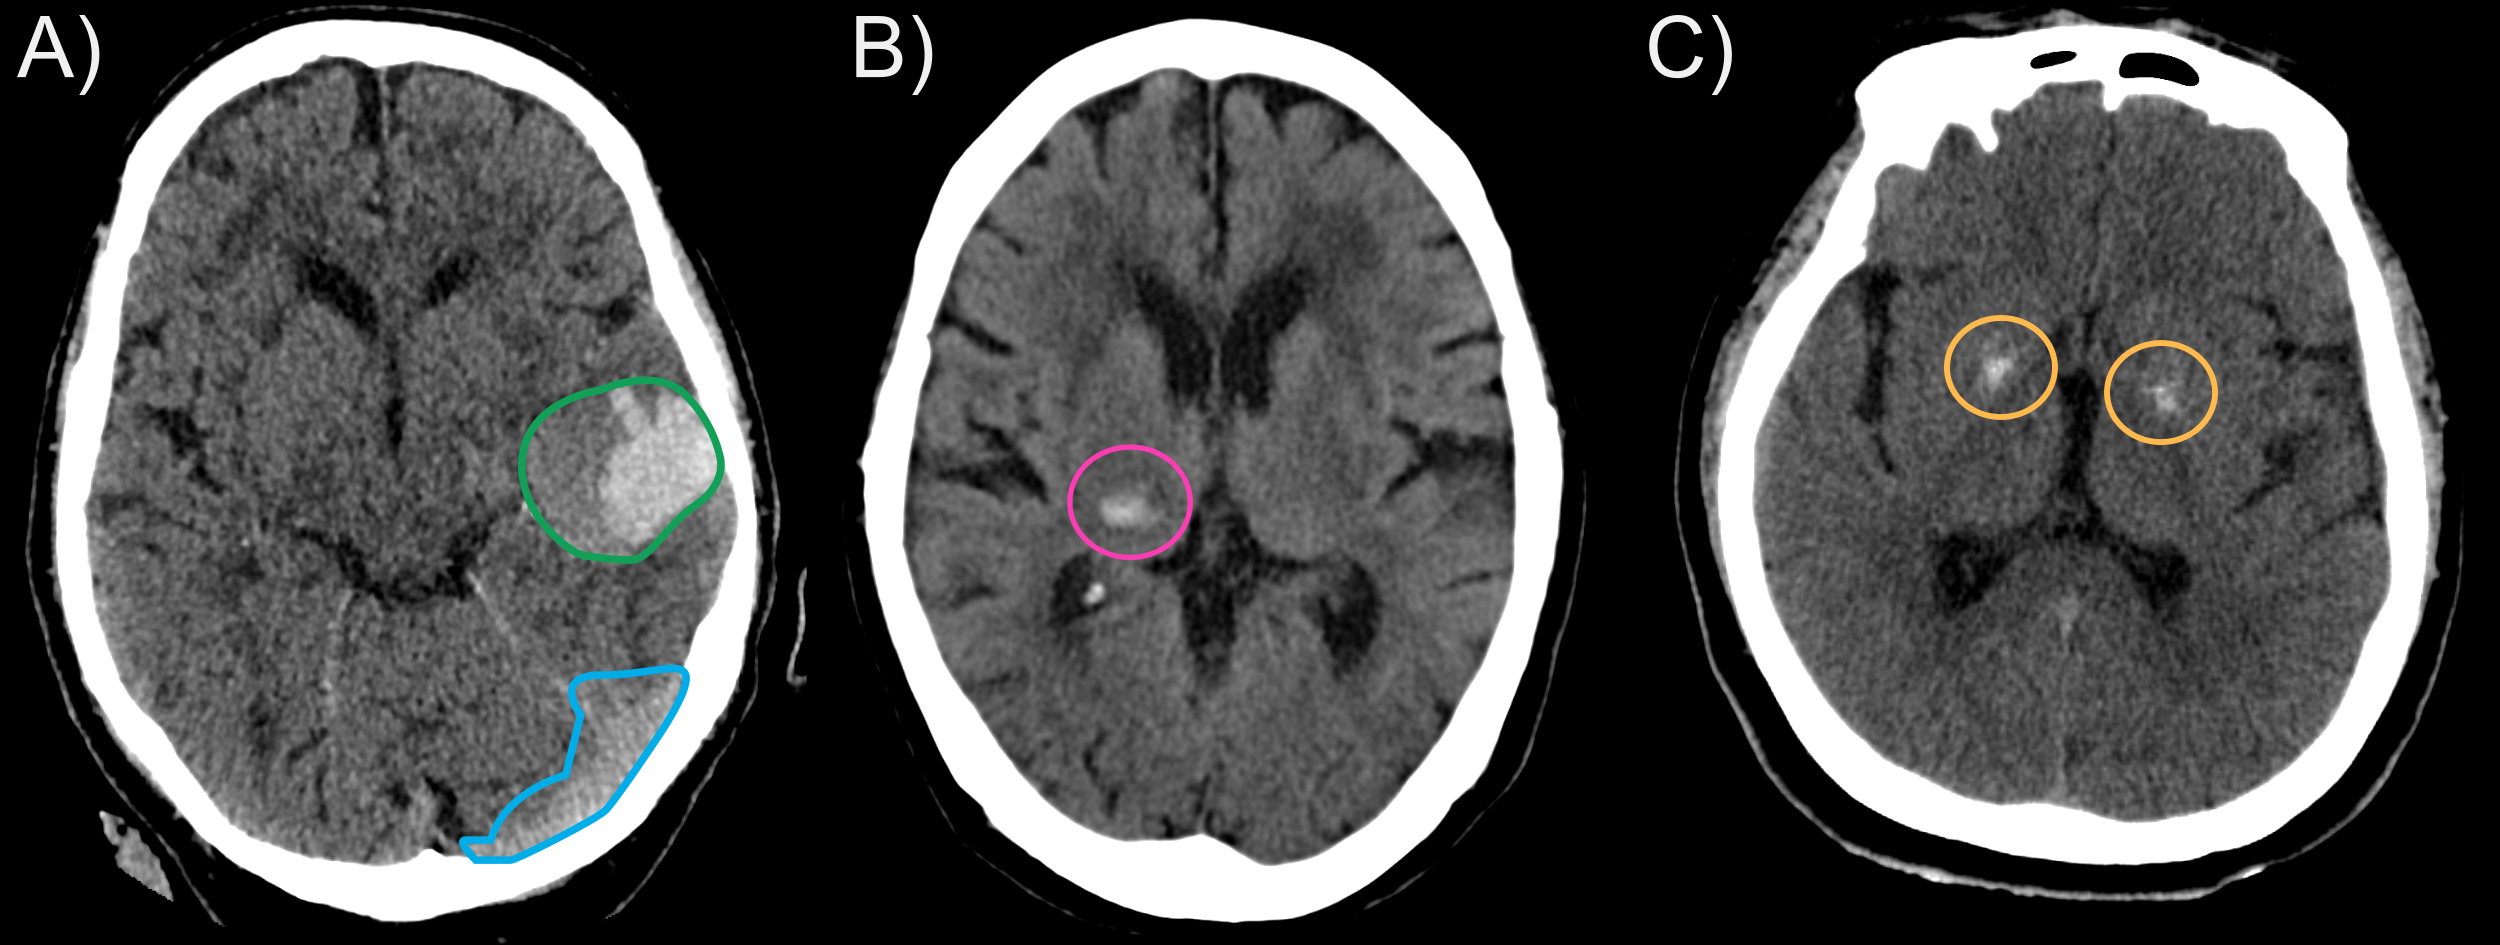

Medical students are often left alone to do these readings due to staff shortages and will often miss lesions [2] or will struggle on hard cases (see Fig. 1). In particular, missed intracranial hemorrhages can have devastating effects on the patient’s odds of survival and future physical autonomy [14]. As a result, there is a clear utility in having expert tools that can focus on a specific part of the whole-body CT and highlight relevant areas.

2.3 Sampling of bleeding

We evaluate methods for bleeding detection using average precision (AP) and average recall (AR) at IoU thresholds of 10% and 30%. Prior studies [1] suggest that using a threshold of 10% IoU is sufficient, as IoU is more penalizing in 3D and clinical applications only require a coarse localization. However, having such a low threshold is problematic for bleeding detection, as their volume can vary greatly. In particular, a bounding box predicted for a given bleeding could easily overlap with a smaller neighboring bleeding. At a low 10% IoU threshold, this bounding box can often sufficiently overlap the second bleeding to be counted as a positive match for both objects. This can be particularly troublesome if the first larger bleeding was in fact a false positive (see Fig. 1 A)). To mitigate this issue, we also provide all results at a 30% IoU threshold.